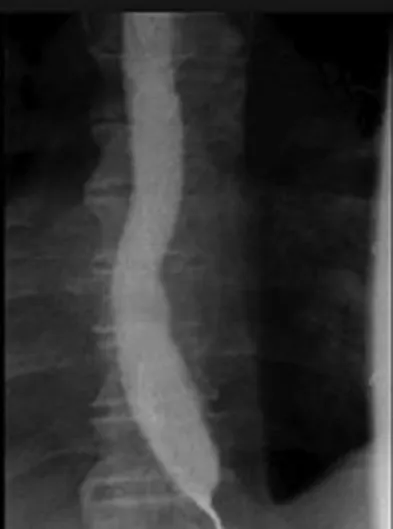

- There is failure of relaxation of smooth muscle at the lower esophageal sphincter.

- Achalasia results from progressive degeneration of ganglion cells in the myenteric plexus in the esophageal wall, leading to failure of relaxation of the lower esophageal sphincter, accompanied by a loss of peristalsis in the distal esophagus.

- Patients present with dysphagia, regurgitation, and heart burn. Chest pain and weight loss may be...